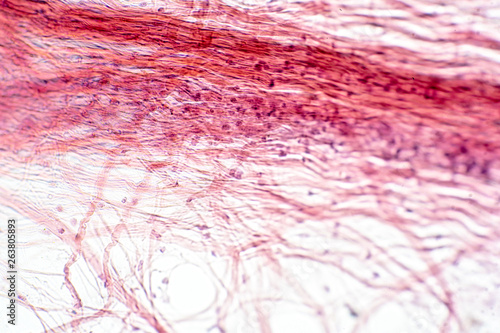

Mikrofotografi - Plakater, Poster, Billeder på lærred